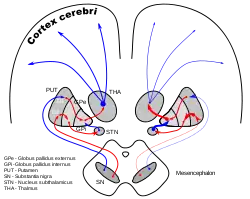

DA-loops in Parkinson's disease | |

The subthalamic nucleus receives its main input from the external globus pallidus (GPe),[8] not so much through the ansa lenticularis as often said but by radiating fibers crossing the medial pallidum first and the internal capsule (see figure). These afferents are GABAergic, inhibiting neurons in the subthalamic nucleus. Excitatory, glutamatergic inputs come from the cerebral cortex (particularly the motor cortex), and from the pars parafascicularis of the central complex. The subthalamic nucleus also receives neuromodulatory inputs, notably dopaminergic axons from the substantia nigra pars compacta.[9] It also receives inputs from the pedunculopontine nucleus.

Efferent targets

The axons of subthalamic nucleus neurons leave the nucleus dorsally. The efferent axons are glutamatergic (excitatory). Except for the connection to the striatum (17.3% in macaques), most of the subthalamic principal neurons are multitargets and directed to the other elements of the core of the basal ganglia.[10] Some send axons to the substantia nigra medially and to the medial and lateral nuclei of the pallidum laterally (3-target, 21.3%). Some are 2-target with the lateral pallidum and the substantia nigra (2.7%) or the lateral pallidum and the medial (48%). Less are single target for the lateral pallidum. In the pallidum, subthalamic terminals end in bands parallel to the pallidal border.[10][11] When all axons reaching this target are added, the main efference of the subthalamic nucleus is, in 82.7% of the cases, clearly the internal globus pallidus (GPi).

Oscillatory and synchronous activity[14][15] is likely to be a typical pattern of discharge in subthalamic neurons recorded from patients and animal models characterized by the loss of dopaminergic cells in the substantia nigra pars compacta, which is the principal pathology that underlies Parkinson's disease.

Lateropallido-subthalamic system

Strong reciprocal connections link the subthalamic nucleus and the external segment of the globus pallidus. Both are fast-spiking pacemakers. Together, they are thought to constitute the "central pacemaker of the basal ganglia"[16] with synchronous bursts.

Some axons from the lateral pallidum go to the striatum.[18] The activity of the medial pallidum is influenced by afferences from the lateral pallidum and from the subthalamic nucleus.[19] The same for the substantia nigra pars reticulata.[11] The subthalamic nucleus sends axons to another regulator: the pedunculo-pontine complex (id).

The lateropallido-subthalamic system is thought to play a key role in the generation of the patterns of activity seen in Parkinson's disease.[20]